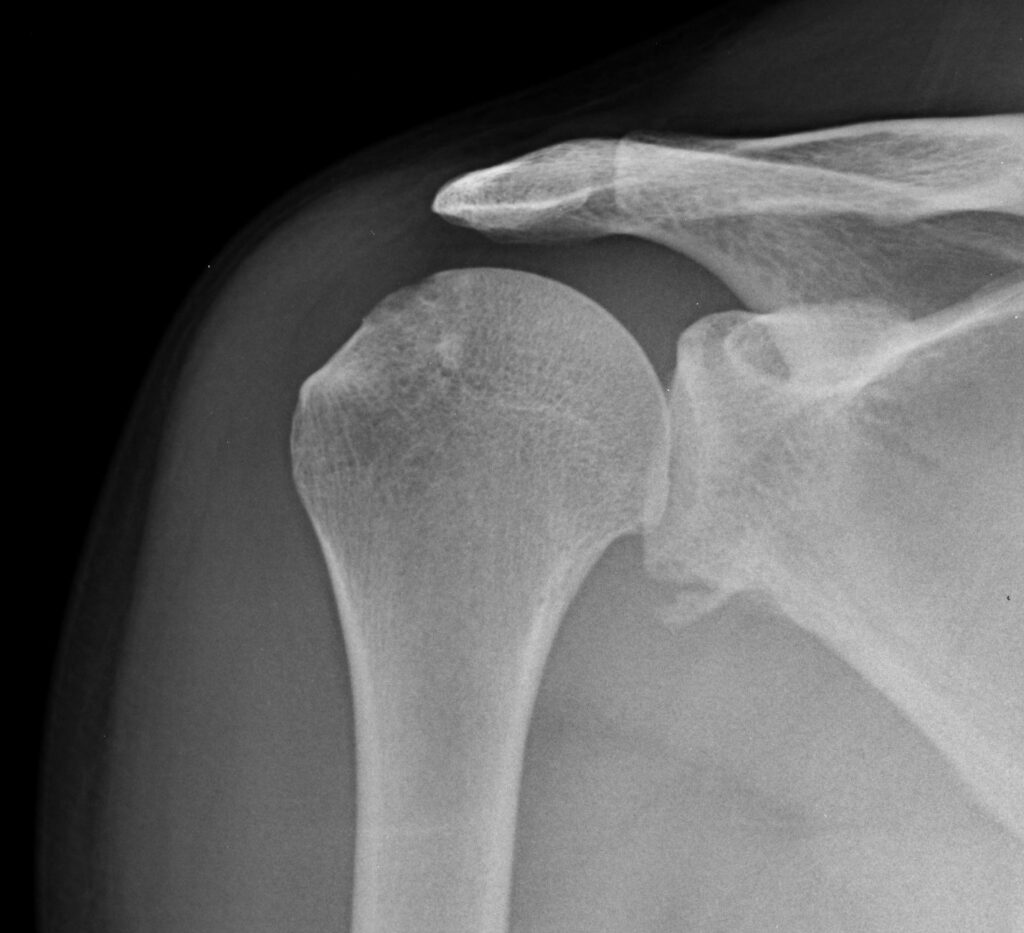

Suggest X-ray following an acute dislocation

Choosing the right therapist starts with them being able to read your X-rays and then plan a treatment plan for you. The therapists at Action Rehab Hand Therapy Clinic are experienced in assessing and reading X-rays.